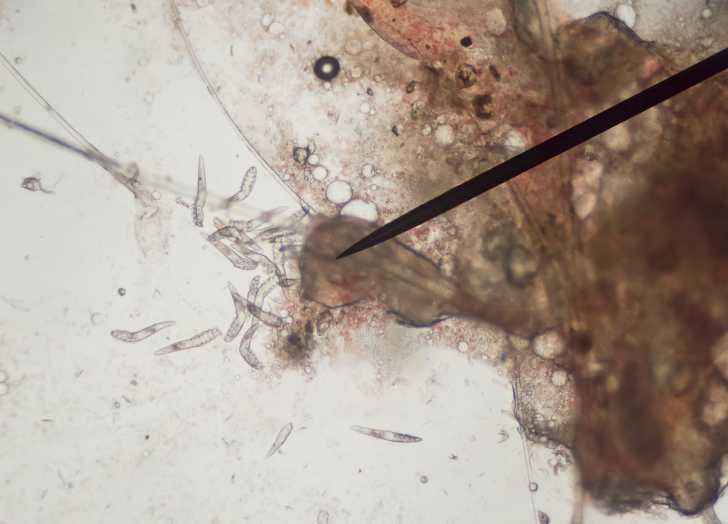

Le meilleur moyen de mettre en évidence Demodex cati consiste à réaliser plusieurs raclages cutanés en périphérie des zones atteintes et à observer les échantillons de peau au microscope. La démodécie est confirmée si l'acarien est présent et de manière suffisamment importante. En effet, s'il n'est implanté qu'en nombre limité, cela ne suffit pas à déclencher les symptômes, et ces derniers ont donc vraisemblablement une autre cause.

Chez le chat, le parasite acarien responsable de la démodécie est soit Demodex cati, soit Demodex gatoi. Ils se distinguent par leur apparence ainsi que par leur localisation cutanée : le premier possède un corps long et loge dans le follicule pileux (c'est-à-dire à la racine du poil), tandis que le second est d'apparence plus courte et vit directement au niveau de l'épiderme.